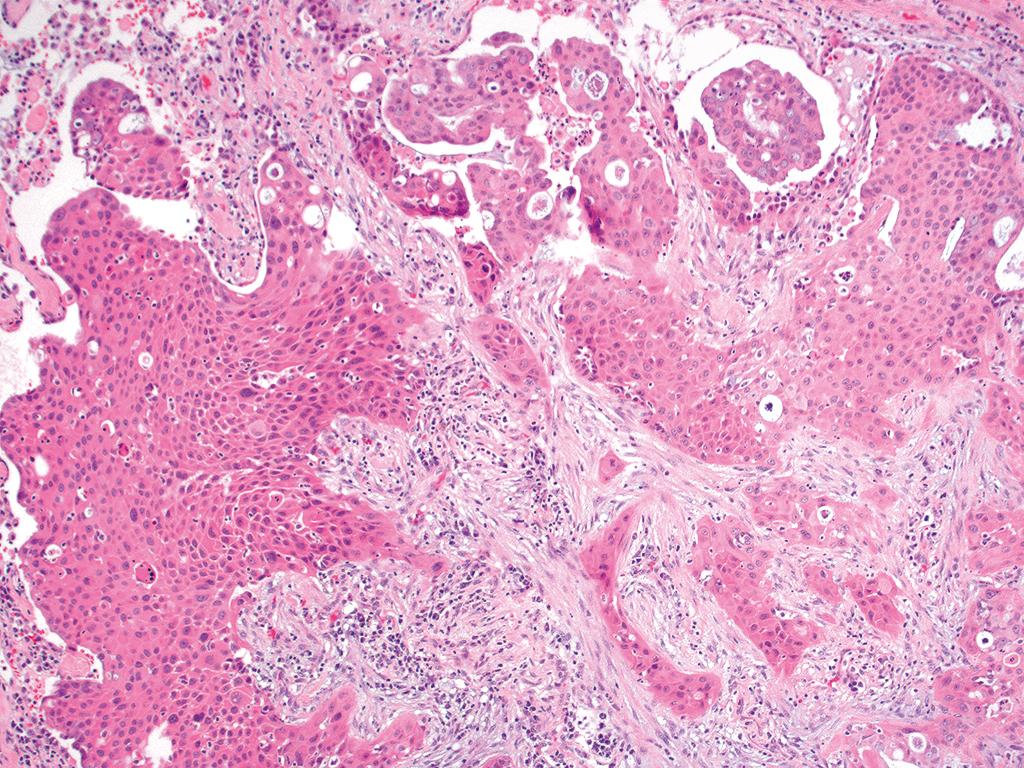

56/ M lung mass. Core biopsy from the lesion. CT and Xray findings attached . Kindly provide your valuable opinions. #pathtwitter #pulmonarypath

NafeesaPath's tweet image. 56/ M lung mass. Core biopsy from the lesion. CT and Xray  findings attached . Kindly provide your valuable opinions. #pathtwitter #pulmonarypath